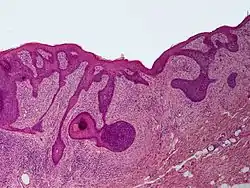

الورم الليفي المحيط بالجريب (بالإنجليزية: Perifollicular fibroma) هو حالة جلدية على شكل ورم حميد وغالبا ما يصاحبه تلون بالجلد وعادة ما يصيب الوجه وأعلى الجذع.[1]:674[2]